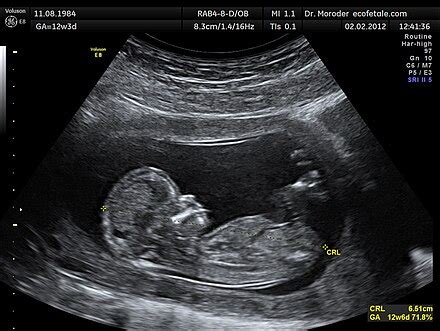

A 35. hétig a baba meglehetősen erősen nőtt. A terhesség minden egyes napján a gyermek nagyobb súlyt szerez, mint a hosszúságát növeli. A magzati test mérete nagyon fontos mutatója az intrauterin fejlődésnek. Speciális ultrahangvizsgálatok elvégzésével az orvosok sok információt kapnak a magzat méretéről. Ha az elmúlt hetekben több információra volt szükségük annak érdekében, hogy felmérjék, hogy a magzat belső szerveinek fejlődése és növekedése megy végbe, most már főként a szülészet megfelelő taktikájának összeállítására van szükség.

A felmérés után következtetést vonnak le, amely a baba testének minden mért paraméterét tükrözi. A gyermek terhességének minden egyes szakaszában történő méréséhez az orvosok speciális klinikai jellemzőket használnak. Ehhez meghatározzák a legfontosabb anatómiai paraméterek paramétereit.

A magzat pozíciója a méhben nagyon fontos klinikai indikátor. A magzat méhében való elhelyezkedésének módjától függ a szülészeti taktika kiválasztása. Az orvos kiválasztja a szülészeti segítségnyújtás módját, hogy a születéskor minimális legyen az anyának és a magzatnak a veszélyes születési sérülések és sérülések kockázata.

A baba helyzetét az anya méhében „prezentációnak” nevezik. A prezentáció különböző lehetőségei vannak. Ennek meghatározásához az orvosok feltétlenül azonosítják, hogy hol vannak a magzat legnagyobb részei.

A születés szempontjából a legkedvezőbb a hosszanti fejfájás. Ebben az esetben a gyermek testének feje a születési csatorna felé helyezkedik el. Általában a test többi része "könnyebben" születik, mivel kisebbek, mint a vállak mérete. A medencés prezentáció, amikor a magzat medencéje először a születési csatornára irányul, a prognózis kevésbé örömteli. Ilyen helyzetben nagyon gyakran a szülés során veszélyes születési trauma fordul elő. Fejlődésük csökkentése érdekében az orvosok gyakran császármetszést végeznek. A keresztirányú helyzet, amikor a magzat a szülőcsatorna hossztengelye mentén helyezkedik el, szintén kevésbé kedvező. Ebben az esetben a gyermek minden nagy része merőleges a születési csatornára. Független szülés, ilyen előadás nagyon veszélyes.

A 35. hétig a baba pozíciója a méhben általában állandó. Az a valószínűség, hogy a magzat újra megfordul, de már nagyon jelentéktelen.